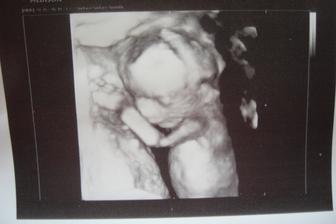

lucia_marek

14. feb 2015

Som kristian a velmi sa teším na moju mamičku a ocinka